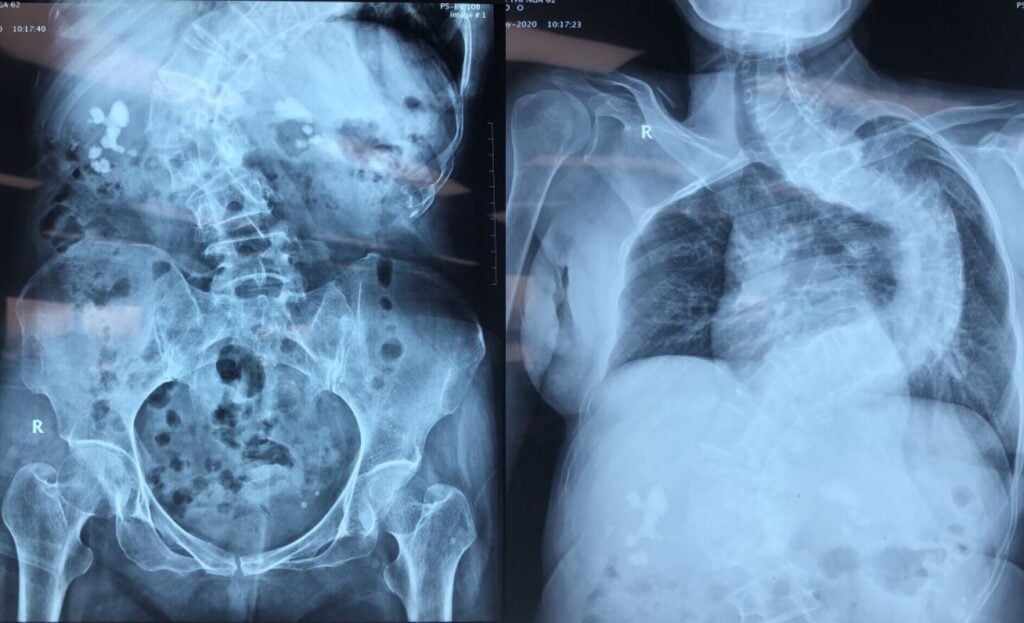

Phương pháp chẩn đoán bệnh

Để chẩn đoán bệnh sỏi thận một cách chính xác nhất, nền y khoa hiện nay thông dụng với 4 phương pháp:

- Thực hiện xét nghiệm nước tiểu

- Tiến hành chẩn đoán bằng hình ảnh

- Thực hiện chẩn đoán phân biệt trên lâm sàng

- Xác định các thành phần cấu tạo sỏi